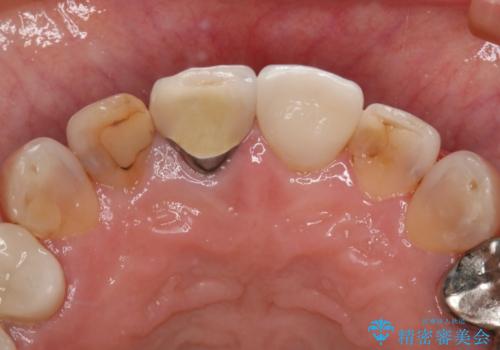

- 右上2番の審美性改善を主訴に来院された患者様です。

切削量と前歯ということからオールセラミッククラウンでの治療を選択しました。